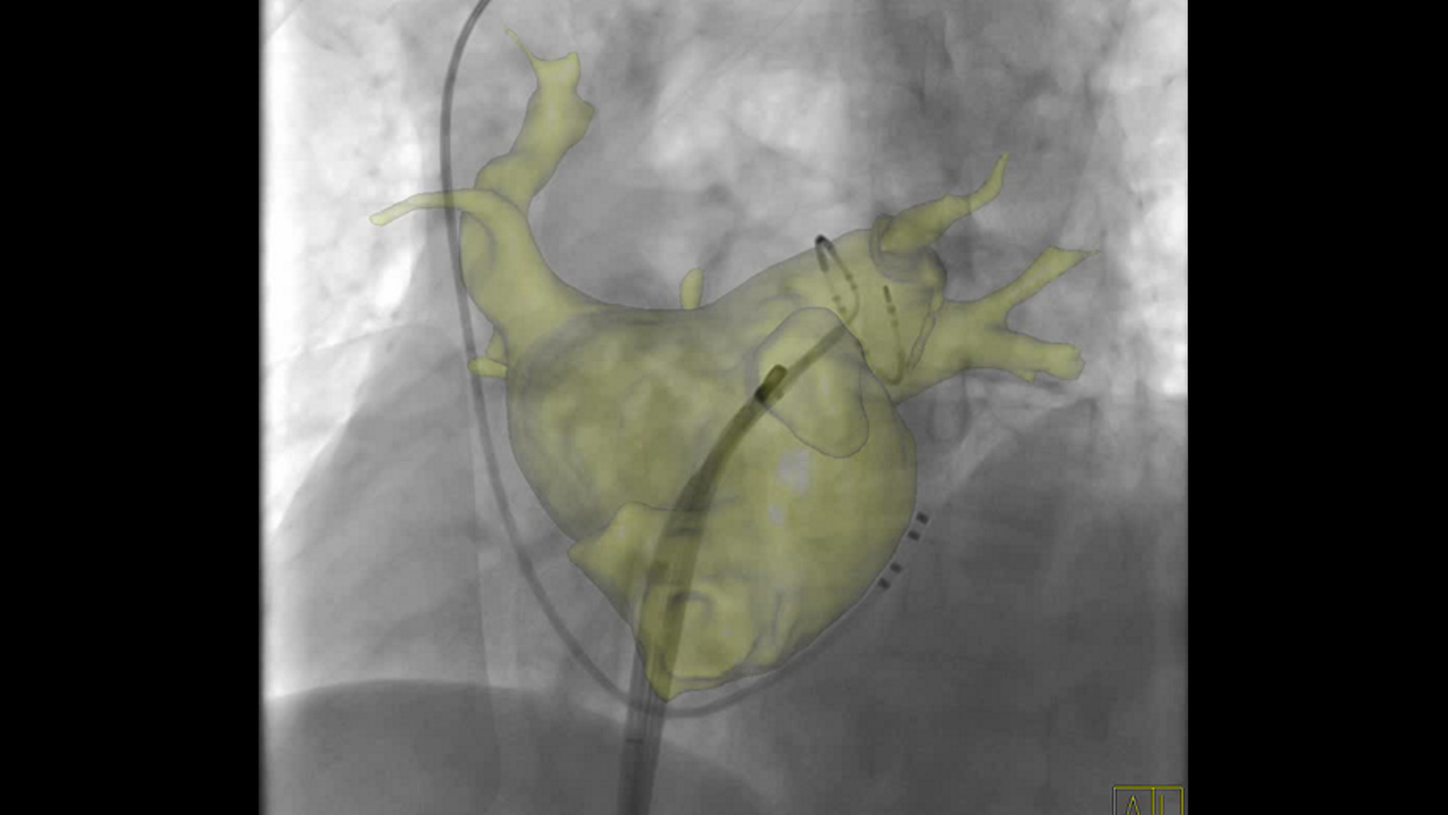

ARTIS icono Structure Scout

Material-specific imaging with Structure Scout

Structure Scout enables improved device visibility supporting ALARA dose due to material-specific optimization of imaging parameters.

With new devices and new materials appearing all the time, image-guided therapy is facing new challenges. Structure Scout adjusts the X-ray spectrum to material-specific acquisition parameters and optimizes visibility of materials, devices, vessels, and background structures independent of procedure or material type with our embedded structure-sensitive algorithm.